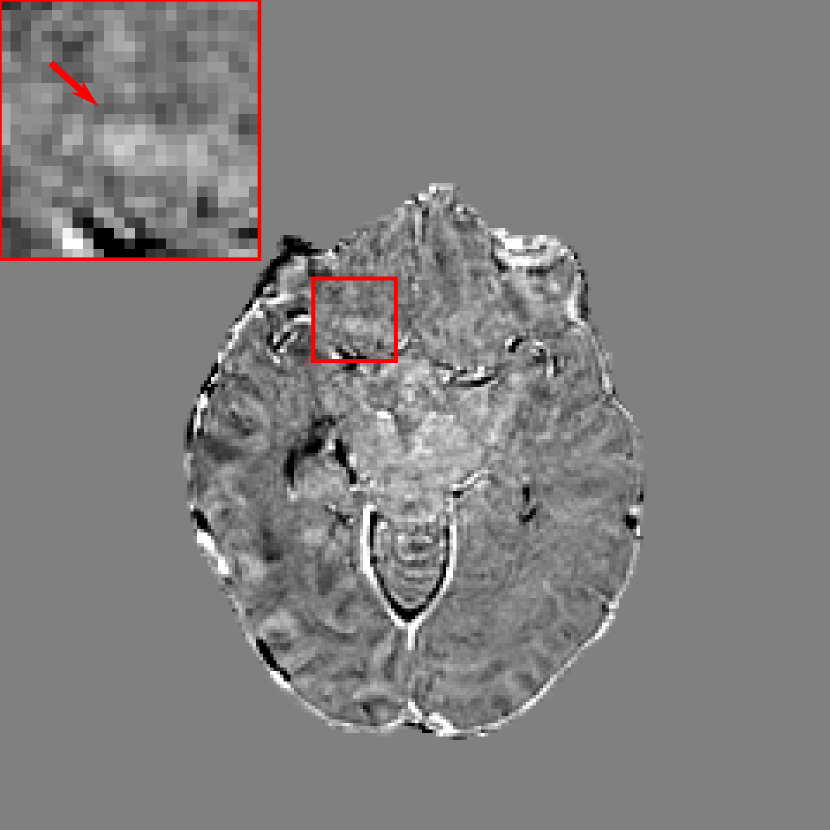

Figure 2: Exemplary images acquired from different time points: (a) temporal prior image; (b) current main image, where the contour indicated by the arrow is segmented incorrectly as a metastasis by a neural network that used the prior image as an additional channel as opposed to an additional pathway; (c) difference between (a) and (b), where the bright region indicated by the arrow is the main cause for the incorrect segmentation.

In contrast-enhanced MRI images with 3D volumetric gradient echo imaging (e.g., BRAVO, GE Healthcare; MPRAGE, Siemens Healthcare; 3D TFE; Philips Healthcare) 36, many structures such as blood vessels are also enhanced by contrast agents. Hence, they have similar appearance to metastases in the regard to intensity, shape, and size in 2D intersectional planes. As a consequence, it is very challenging for human experts to distinguish them. BM differ from blood vessels in several aspects. One is that although they appear similar in 2D intersectional planes, they have distinct morphological appearance in 3D space. For example, enhanced vascular structures are tube-like structures with bifurcations, while the majority of BM are sphere-like structures 37. Therefore, 3D neural networks are advantageous over 2D networks to extract 3D features. In addition, BM have relatively larger morphological changes over time than normal tissues. Without treatment BM volume size typically grows faster than normal tissues due to the high proliferation rate of tumor cells. With treatment BM volume sizes change depending on treatment response, for example, volume size decreases in regression, increases in progression, and oscillates (increases first and later decreases) in pseudo-progression 38. In radiation therapy, patients have regular follow-up MRI scans in approximately every 4-6 weeks. Therefore, by comparing two images acquired from two time points, if a high contrast structure emerges or grows, this structure has high confidence to be a metastasis. To integrate such temporal prior information in deep learning, two potential ways are possible: using the temporal prior volume as an additional input channel or as an additional input path. As anatomical structures imaged at different time points cannot be perfectly registered to the same position, using temporal prior volumes as an additional channel will result in a high FP rate. An example is displayed in Fig. 2, where a normal tissue region indicated by the arrow in Fig. 2(b) is segmented incorrectly as a metastasis. Such mis-segmentation is mainly caused by the imperfect registration, since high intensity difference is observed in the corresponding region of the difference image (Fig. 2(c)). To avoid such problem, in this work we propose to put the temporal prior volume as an additional input path, where features from two time points are merged at deep layers. For distinction, the modified DeepMedic architecture is called DeepMedic+ in this work. The overall DeepMedic+ architecture is displayed in Fig. 3, where the normal resolution subvolumes from both the prior and main datasets as well as two low resolution subvolumes from the main dataset are fed into DeepMedic+. Note that for volumes without any temporal prior, an empty prior volume with zero values is used.